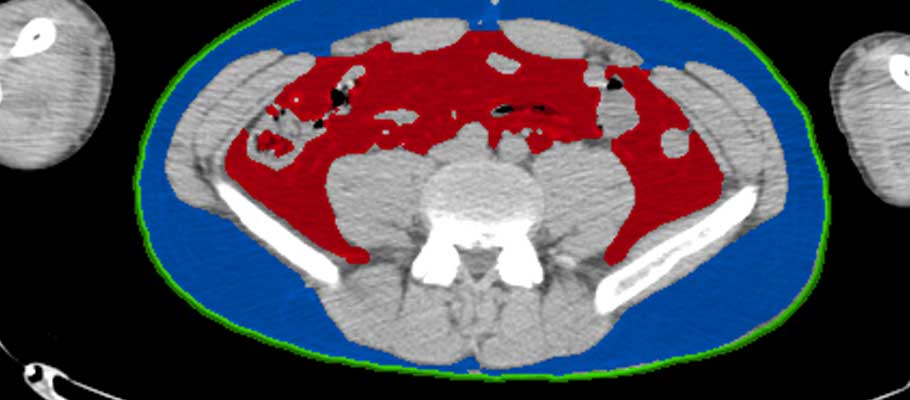

内臓脂肪自動計測

成人病リスクを数値化

サルコペニアプロジェクト

内臓脂肪・皮下脂肪領域の抽出と筋肉量計測